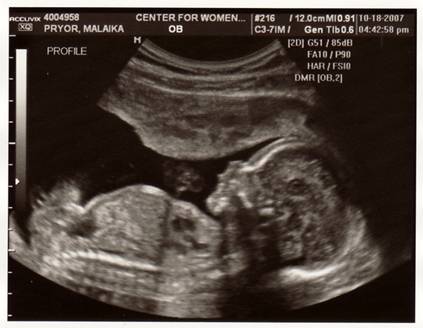

УЗ-сканирование плода (УЗ-диагностика) - исследование состояния плода с помощью ультразвукового аппарата является одним из основных методов ПД (рис. 7.4.5, 7.4.6). УЗ исследование позволяет выявить 80 - 98 % плодов с анатомическими пороками и в настоящее время широко используется в нашей стране для скрининга патологии беременности. Метод особенно информативен на сроке 18 - 20 недель беременности.

Рис. 7.4.6. Изображение 3D УЗ-исследования